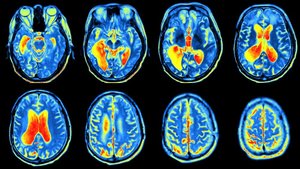

Tam olarak ne kadar radyasyon alınıyor?

Sadece PET'de alinan radyasyon miktari cok dusuk demek yerine karsilastirma yapmak iyi olabilirdi. Ornegin, tam olarak rakami hatirlamiyorum ama bir doktor, bir PET'den sonra 50 rontgen cektirmis gibi olursun demisti.